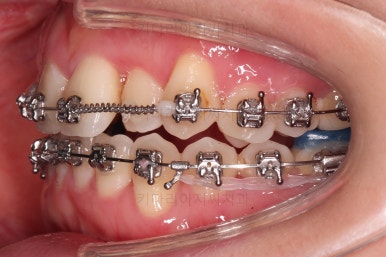

중간평가 이후 남아있는 공간은 일부 어금니를 앞으로 당겨오면서 개선하기로 했습니다.

미니스크류를 이용해 주었고요.

그래야 중심선이나 입매에 더 도움이 되기 때문이죠.

적절하게 디테일을 손보고 마무리를 합니다.

중간중간 보철된 치아도 있고, 위아래의 중앙선까지 100% 맞기는 힘든 상황이었지만 가급적이면 매우 잘 맞춰 드렸고요.

교합이라던지 가지런한 느낌도 좋네요.

우측만 위아래 뽑았지만 기능에는 문제 없이 교합을 마무리 했습니다.